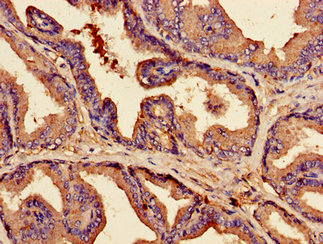

Immunohistochemistry of paraffin-embedded human prostate tissue using CSB-PA13119A0Rb at dilution of 1:100